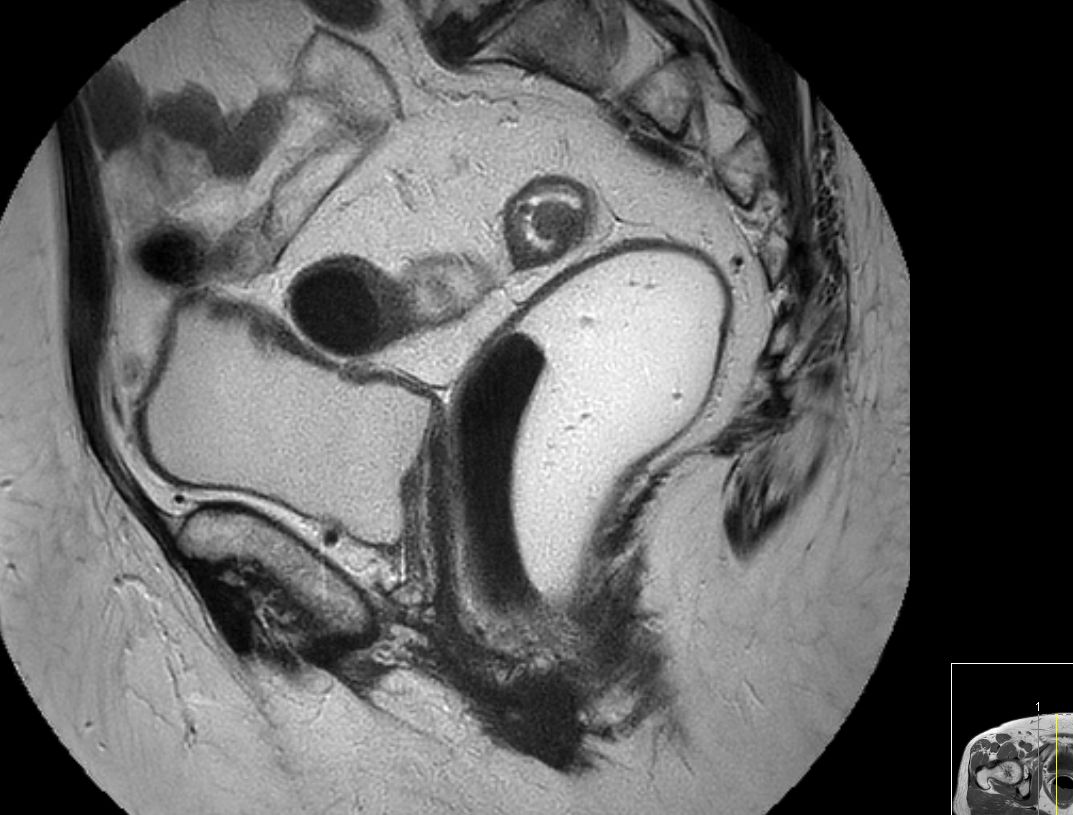

| MRT: T2-Tumor | 61-jähriger Mann mit G2-Adenokarzinom des Rektums von 8-14 cm. T2-Tumor ohne Hinweis auf Wandüberschreitung.![]() |

![]() |

|